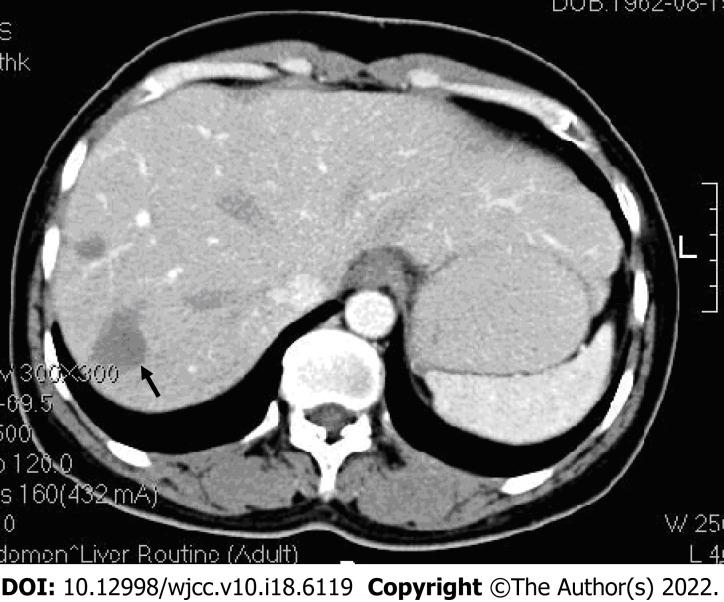

A 46-year-old woman with abdominal discomfort and elevated serum carcinoembryonic antigen was found to have multiple low-density lesions in the liver and lung on computed tomography (CT) evaluation. An ultrasound-guided fine needle aspiration biopsy revealed a fibrous stroma with dendritic cells, containing intracellular vacuoles. Immunohistochemical staining found that the tumor cells were positive for CD34, CD31, and factor VIII-related antigen. The patient received four courses of combined chemotherapy and was followed-up for 13 years, at which time the patient was in stable condition without disease progression and a confined neoplasm, as evidenced by CT scans.

一名 46 岁女性,有腹部不适且血清癌胚抗原升高,计算机断层扫描(CT)评估发现肝脏和肺部有多个低密度病变。超声引导下细针穿刺活检显示有含树突状细胞的纤维性基质,细胞内有液泡。免疫组织化学染色发现肿瘤细胞对 CD34、CD31 和因子 VIII 相关抗原呈阳性。该患者接受了四个疗程的联合化疗,并随访 13 年,此时患者病情稳定,无疾病进展且肿瘤局限,CT 扫描证实了这一点。